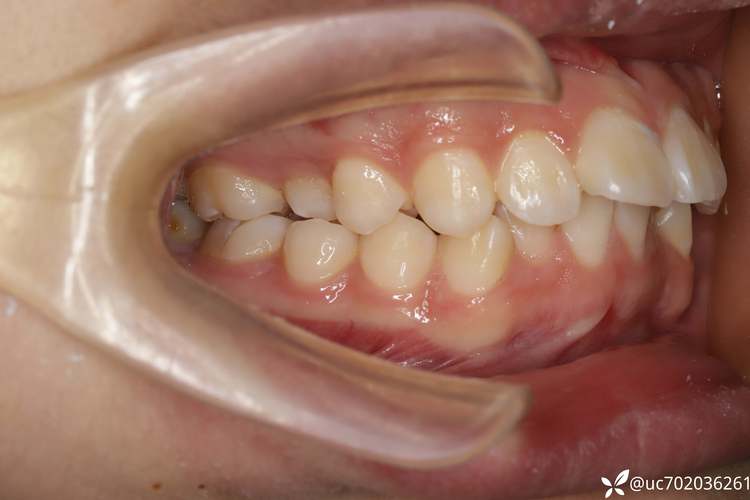

牙齿在口腔中的排列需遵循“牙量与骨量的协调原则”——即牙齿总宽度(牙量)与颌骨提供的容纳空间(骨量)需匹配,当牙量大于骨量时,会出现牙齿拥挤、排列不齐;若同时伴随前牙前突(“龅牙”)、咬合过深(深覆合)或面部软组织前凸等问题,单纯通过扩弓、邻面去釉等非拔牙方式往往难以获得稳定效果,此时拔牙便成为“创造空间、调整咬合、改善面型”的关键选择。

对于中度以上拥挤(拥挤度超过8mm),拔除1-2颗前磨牙(通常为第一或第二前磨牙)可为内收前牙提供充足空间,既解决拥挤,又能改善牙弓形态;对于前牙深覆盖(上切牙突出下切牙超过7mm)且伴随牙弓狭窄的患者,拔牙后通过前牙向后移动、后牙前移,可同时纠正前突和咬合关系,避免“硬撑”导致的牙齿代偿性移动或复发,部分患者存在“牙性+骨性”双重问题,如上颌前突伴下颌后缩,拔牙配合颌间牵引,能在调整牙齿位置的同时,利用颌骨改建潜力改善面部侧貌。

通过X线头影测量、牙模型分析,计算“牙弓拥挤度”(现有牙弓长度与理想牙弓长度的差值),若拥挤度>4mm,单纯扩弓可能引发后牙颊倾、牙龈萎缩等风险;若拥挤度>8mm,通常建议拔牙,牙弓形态(尖圆形、椭圆形、方圆形)需与面部宽度匹配,过窄的牙弓拔牙后可通过调整后牙位置拓宽牙弓,改善微笑曲线。

咬合异常(如反颌、锁颌、深覆合)不仅影响咀嚼功能,还可能导致面部肌肉失衡,II类错颌(上牙前突、下牙后缩)患者拔除上颌前磨牙,可利用“滑动机制”内收上前牙,纠正咬合的同时改善“凸面型”;III类错颌(下牙前突、上牙后缩)患者若为牙性因素,拔除下颌前磨牙可为后牙前移、前牙内收创造空间,改善侧貌凹陷。